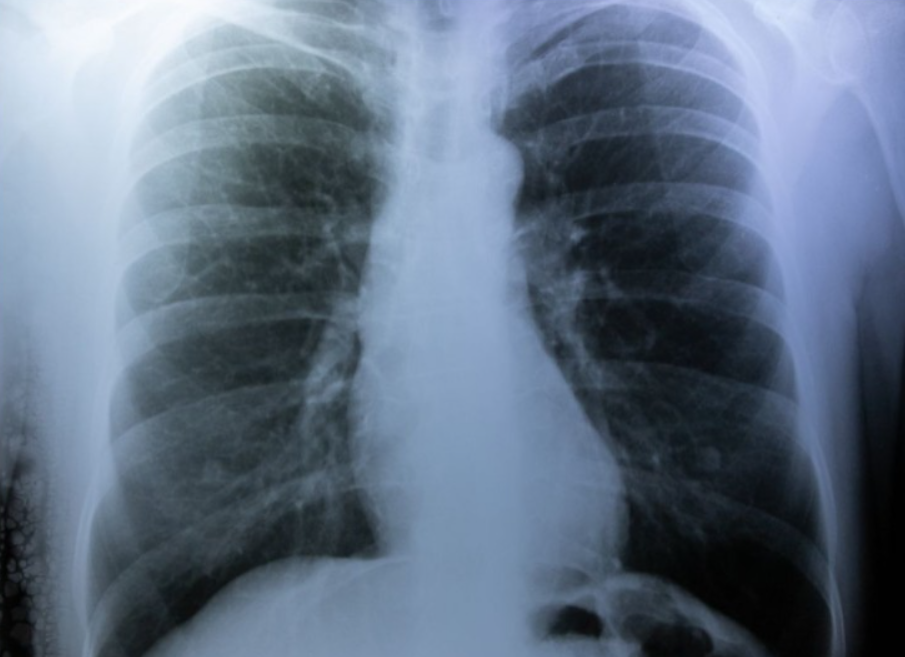

폐 기흉(Pneumothorax)은 폐에서 공기가 흉강으로 새어 나가 폐가 축소되는 상태를 말합니다. 이는 폐에서 공기가 비정상적으로 흘러나가 흉강에 공간이 형성되어 발생하며, 일반적으로는 흉곽 속에 위치한 폐에 손상이나 관련 질환이 있을 때 발생합니다. 폐 기흉은 호흡곤란, 가슴 통증 및 기타 증상을 유발할 수 있으며, 적절한 관리와 예방이 중요합니다.

폐 기흉은 폐에서 공기가 비정상적으로 흘러나가 폐가 축소되는 상태를 의미하며, 가슴 통증, 호흡곤란 등의 증상을 유발할 수 있습니다. 외상, 폐 질환, 압력 변화 등이 주된 원인으로 작용할 수 있으며, 예방을 위해 안전장비 착용과 의료 전문가의 지속적인 상담이 필요합니다. 적절한 관리와 조기 발견은 폐 기흉의 합병증을 예방하고 치료에 중요한 역할을 합니다. 무엇보다도, 폐 기흉에 대한 적절한 지식과 의학적 지원을 통해 환자들의 건강을 돌보는 것이 필요합니다.